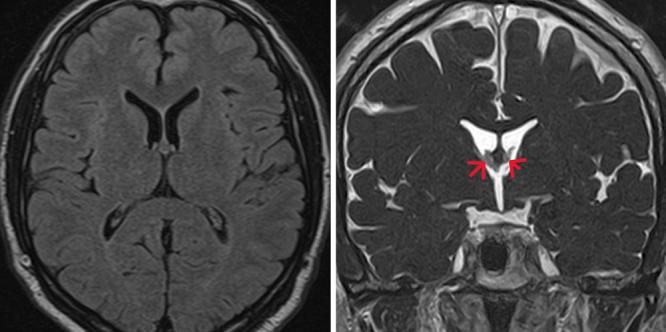

Colloid cyst of the third ventricle: a rare case of spontaneous regression. Illustrative case.

The following case presents a rare and curious instance of a spontaneously regressing CC. This represents the 11th case ever reported about an extremely rare occurrence: the spontaneous regression of a previously diagnosed CC in the third ventricle.

Carefully selected asymptomatic CCs can be monitored through regular imaging studies and neurological examinations. If regression of the cyst is observed, physicians should not be surprised, as this event, although rare, has been documented and published in 11 cases, including this one. https://thejns.org/doi/10.3171/CASE24498.